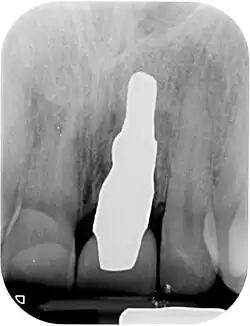

RAIs are custom made to perfectly fit the tooth socket of a specific patient immediately after tooth extraction. Therefore every implant is unique. As an optimised root-form it is much more than a simple 1:1 replica of a tooth. Since it exactly fills the gap left after the tooth is extracted, surgery is rarely needed. The implant can be produced from a copy of the extracted tooth, an impression of the tooth socket, or from a CT scan or CBCT scan.[7] The advantage of a CBCT scan is that the implant can be produced before extraction. With the former methods, it takes one or two days to fabricate an implant.

Treatment consists of three steps:[5]

- Obtain the 3D form of the tooth to be replaced. This is done either through careful tooth extraction and scanning of the root, taking an impression of the tooth socket, or a pre-op CBCT scan. The root analogue implant is produced using modern CAD/CAM technology, based on the principle of differentiated osseointegration;

- Atraumatic extraction of the hopeless tooth;

- Placement of the root analogue implant by tapping it in. In general, no surgery is necessary. In particular, no sinus lift or invasive surgery is ever necessary. The implant is placed immediately if it has been produced beforehand from a CBCT scan, or the next day if root has to be scanned or an impression of the socket is used. A protective splint is fitted to protect the implant during the healing period.

Recovery time is very fast as neither soft nor hard tissue is traumatised. Typically, even the day after implant placement there is no swelling, bruising or pain. After 8–12 weeks' healing period, the final crown may be fitted by a family dentist.